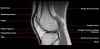

무릎 관절의 MRI 단면영상2016-08-31카테고리 106원본 보기1. Sagittal section 2. Coronal section 3. Axial section ← 이전 글전방 족근관증후군(Anterior tarsal tunnel syndrome) : 발등이 꽉 끼는 구두를 신은 후부터 발등을 누르면 아프고 엄지와 검지 발가락 사이가 저려요다음 글 →흉곽출구증후군(Thoracic outlet syndrome) : 팔이 아프고 감각이 떨어지면서 저려요같은 카테고리 글2017-06-10톰슨 검사(Thompson test) : 아킬레스건 파열을 조사하는 테스트2017-06-09Apley 압박 검사(Apley compression test) : 반월상 연골 손상을 조사하는 테스트2017-06-08맥머레이 시험(McMurray test) : 반월상 연골 손상을 조사하는 테스트← 전체 글로 돌아가기